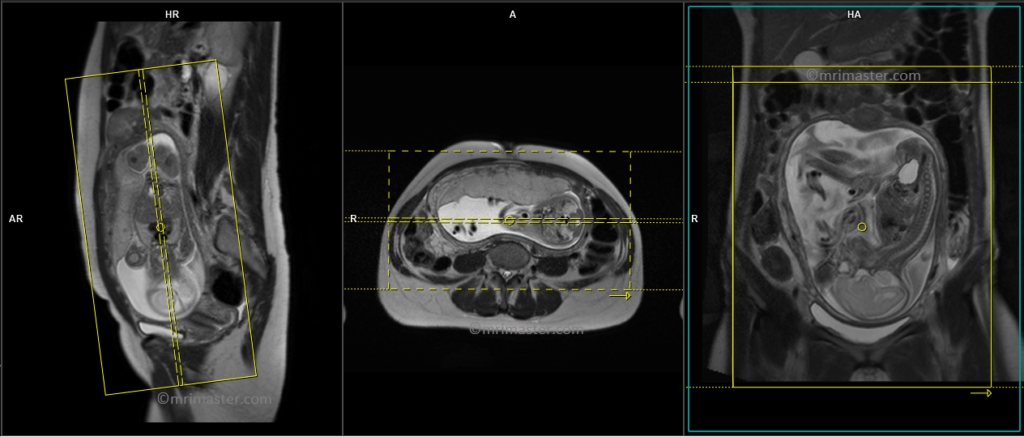

T2 HASTE sagittal 6 mm Respiratory gated

Begin by planning the sagittal slices on the coronal localizer and position the block parallel to the gravid uterus. Verify the positioning block in the other two planes to confirm proper alignment. It is essential to provide an appropriate angle in the axial plane, which should be perpendicular to the gravid uterus. The number of slices should be sufficient to cover the entire abdomen and pelvis, from right to left. The field of view (FOV) must be wide enough to encompass the whole abdomen and pelvis, typically ranging from 400 mm to 480 mm. However, it is important to note that these scans usually take approximately 35 to 40 seconds, which can be challenging for a pregnant woman to hold her breath. To address this issue, we perform the scan under respiratory gating. There are two options for respiratory gating: the liver dome method or the table respiratory sensors. In our department, we utilize the table respiratory sensor.

T2 HASTE coronal 6 mm Respiratory gated

Plan the coronal slices on the sagittal localizer and position the block parallel to the gravid uterus. Verify the positioning block in the other two planes for proper alignment. An appropriate angle should be set in the axial plane, running parallel across the gravid uterus. The number of slices should be sufficient to cover the entire abdomen and pelvis, from the anterior abdominal wall to the spinous process of the vertebrae. The field of view (FOV) must be large enough to encompass the entire abdomen and pelvis, typically ranging from 400 mm to 480 mm. However, it is important to note that these scans usually take approximately 30 to 35 seconds, which can be challenging for a pregnant woman to hold her breath. To address this issue, we perform the scan under respiratory gating. There are two options for respiratory gating: the liver dome method or the table respiratory sensors. In our department, we utilize the table respiratory sensor.

T2 HASTE axial 6 mm Respiratory gated

Plan the axial slices on the sagittal scans and angle the position block perpendicular through the gravid uterus. Verify the positioning block in the other two planes for proper alignment. An appropriate angle should be set in the coronal plane, running perpendicular across the gravid uterus. The number of slices should be sufficient to cover the entire abdomen and pelvis, from the diaphragm to the pubic symphysis. The field of view (FOV) must be large enough to encompass the entire abdomen and pelvis, typically ranging from 400 mm to 480 mm. However, it is important to note that these scans usually take approximately 40 to 45 seconds, which can be challenging for a pregnant woman to hold her breath. To address this issue, we perform the scan under respiratory gating. There are two options for respiratory gating: the liver dome method or the table respiratory sensors. In our department, we utilize the table respiratory sensor.